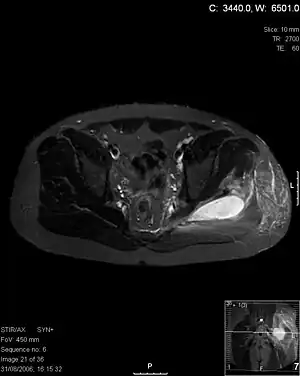

Axial T1 weighted fat suppressed post IV gadolinium contrast enhanced MRI image showing a mutliloculated bacterial abscess in the left gluteal muscle which grew Staphylococcus aureus (methicillin sensitive) thought to be due to tropical pyomyositis.

Coronal fat suppressed post contrast image showing a multiloculated bacterial abscess in the left gluteus minimus muscle due to tropical pyomyositis.

Coronal T2 weighted fat suppressed image showing a multiloculated fluid collection in the left gluteal musculature due to tropical pyomositis in a 12-year-old boy.